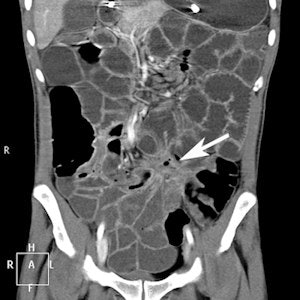

A total of 15 (20.5%) of the 73 patients had positive findings on CTE related to small-bowel pathology, and 12 (16.4%) had nonsmall-bowel pathology that could explain clinical symptoms. Most prevalent small-bowel findings were in the inflammatory bowel subgroups (either known or suspected), where six (30%) patients out of 20 had signs of active inflammatory bowel disease (IBD).

In the group of patients with known IBD, 3 (37.5% of subgroup) had signs of active inflammation and one patient had perianal fistulae. In the group referred with possible IBD, 3 (25% of subgroup) patients had signs of active IBD, one had ileocecal intussusception and one had a small-bowel mass lesion. This proved to be a hamartoma at histology following surgical resection.